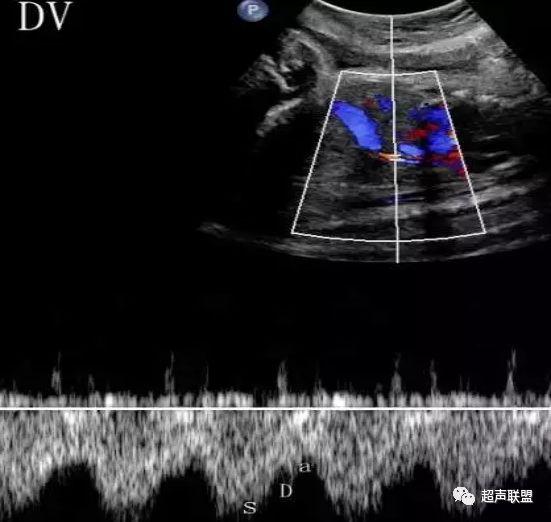

3 胎儿静脉导管

当右心负荷增大,心功能失代偿时,静脉回流受阻,静脉导管a波收缩期流速下降,血流消失甚至倒置。

5、静脉导管:a波消失或反向(见于严重的胎儿宫内缺氧);

3、静脉导管a波反向或消失;

图5 胎儿宫内正常静脉导管

图6 胎儿宫内缺氧时静脉导管a波反向